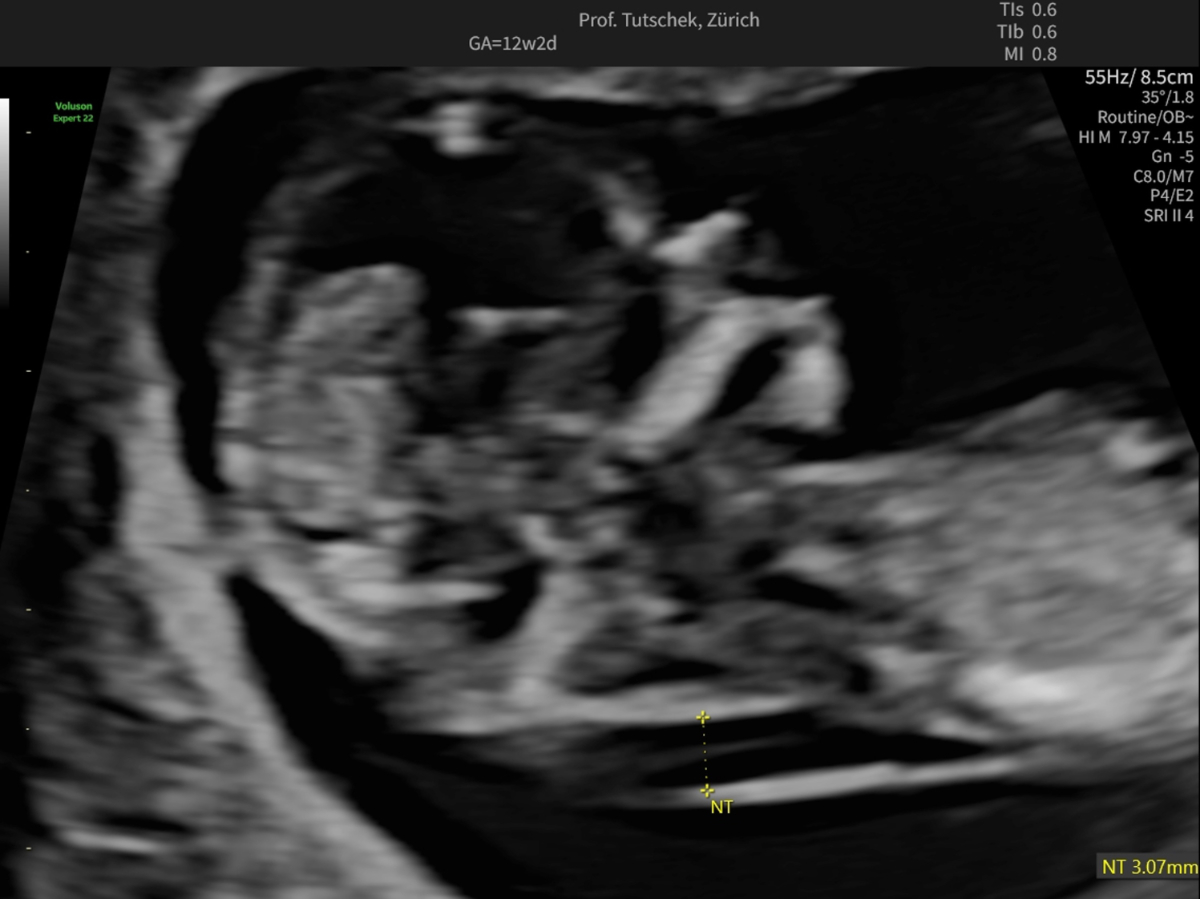

Ultrasound (US) and blood parameters show characteristic deviations in pregnancies complicated by fetal trisomy 21, trisomy 13 and trisomy 18 as well as in many other pathological conditions. Two of three foetuses with trisomy 21 show an increased nuchal translucency (figure 1a-c).

Figure 1cUltrasound measurements during the first trimester ultrasound: measurement of an increased (3.07 mm) nuchal translucency (NT).